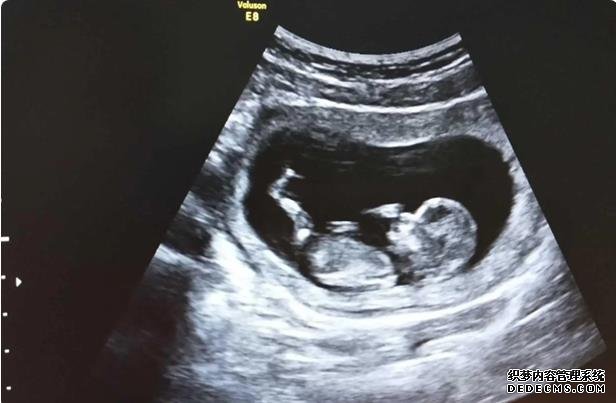

大多數的女性在選擇做試管嬰兒手術的時候,可能也都有自己的一些想法,比如他們在選擇做試管嬰兒手術的過程當中,可能更傾向于第三代試管嬰兒,那么蘇州市立醫院三代試管究竟有此哪一些認知?其實很多人可能在這方面對試管嬰兒的成功率認知并沒有我們想象當中那么多,這種情況下我們要結合自己的實際情況來看一下現有的試管嬰兒的情況。

目前,蘇州有三家具有人類輔助生殖技術資格的醫院,其中兩家可以進行體外受精技術,即蘇州大學第一附屬醫院和蘇州市立醫院,蘇州大學第二附屬醫院只能進行人工授精技術。體外受精技術對醫生的技術和醫院手術實驗有較高的要求,所以我們不僅要關心價格,而且要從醫院的整體水平出發,選擇最合適的醫院。

試管受精的成功率與兩個因素直接相關。一個是年齡。我們都知道,年齡越大,生孩子的可能性就越小。這主要是因為卵子的質量隨著年齡的增長而下降。年齡越大,卵子質量越低,失敗的風險就越高。另一個是醫療水平因素。好醫院的技術成熟度越高,試管受精的成功率就越高。